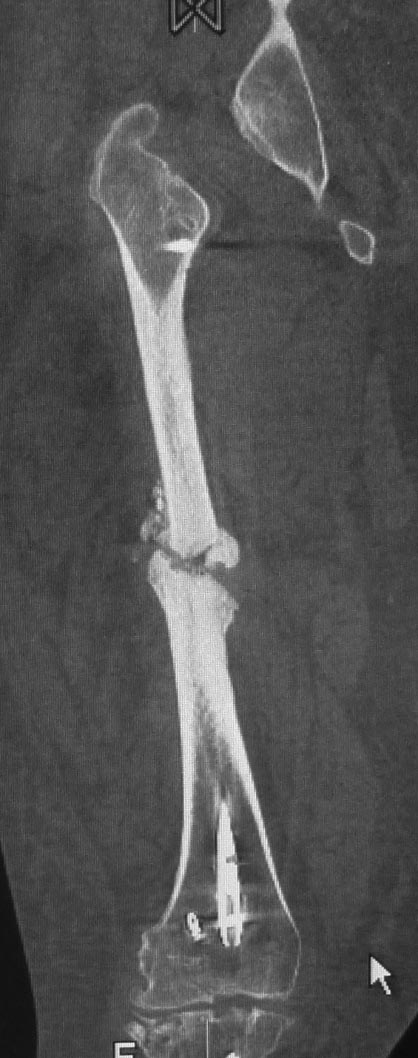

Уважаемые коллеги. Хотелось бы выслушать мнения и советы по представленному случаю. Пациент 42 лет, вес 130 кг, рост около 160 см, сахарный диабет в легкой форме (впервые выявлен после травмы). Травма в феврале 2011 г. - упал с мотоцикла на отдыхе за рубежом. По возвращении в Россию был прооперирован в несколько этапов: в марте 2011 г. - остеосинтез обеих костей правого предплечья пластинами по поводу открытого перелома; интрамедуллярный остеосинтез правого бедра; остеосинтез проксимального конца правой большеберцовой кости. В апреле 2011 г. был доставлен 1 блокирующий винт в дистальное отверстие гвоздя и выполнена пластика крестообразных и наружной боковой связок левого коленного сустава. В феврале 2012 г. были удалены фиксаторы с проксимального конца правой большеберцовой кости и выполнена пластика крестообразных и наружной боковой связок правого коленного сустава. За это время пациент смог начать ходить, сначала с костылями, а затем - без дополнительной опоры. Летом 2013 г. решил укрепить ноги с помощью подъемов пешком на пятый этаж. В результате - усталостная рефрактура правого бедра и перелом интрамедуллярного гвоздя. 09.09.2013 - реостеосинтез латеральным бедренным гвоздем с пластикой костной аутостружкой + СhronoS. Сейчас, через 6 мес после операции, может ходить без дополнительной опоры, периодически беспокоит болезненность в области правого бедра. На сегодняшних КТ - отсутствие признаков консолидации. Нужно ли что то делать и, если да, то что? Рассматриваемые варианты: повторная костная пластика дефекта; доставить блокирующие винты (самый проксимальный винт был удален через 3 мес после операции). Еще раз менять гвоздь не хотелось бы. На представленных снимках: бедро в 2011 г., через несколько мес после операции; в 2012 г., на стадии консолидации; со сломанным гвоздем; сразу после повторной операции (3 рентгенограммы). Все КТ - сегодняшние. Заранее спасибо за ответы.

Второй гвоздь был на 2 см длиннее и на 1 номер толще предыдущего. По-моему десятка.В принципе какая разница? Впечатление о том, что тонковат, ведь не зависит от реальной толщины гвоздя. Канал не рассверливал. Но забивал с трудом.

Мне тоже показалось, что тонковат. Но, раз операция нежелательна, надо ждать и лечить консервативно. При неуспехе - на мой взгляд, замена стержня на более толстый с рассверливанием канала и, возможно, костной пластикой.

Сергей, а ?ожно по подрбнее о костной пластике при в сентябре 2013 приреостеосинтезе. Что это была за пластика? доступ? было ли рассверливание? диаметр гвоздя?

ждать-не ждать? Срочности нет, подождать можно, но активно, т.е. оценить клиническую и рентгенологическую динамику: два месяца назад, сейчас и еще через пару месяцев. Уменьшатся боли, появится более убедительная мозоль - ждите и наблюдайте дальше. Отсутствие положительной динамики можно приравнять к отрицательной динамике. Очевидно, что здесь имеют место быть обе проблемы: биологическая -мозоль слабая и механическая - тонкий гвоздь, недостаточная стабильность. Тогда -удаление, рассверливание (очень аккуратное, по 0.5 мм шаг, острыми фрезами, чтобы не пожечь кость - кортикал толстый и довольно прочный). Для 130 кг диаметр гвоздя минимум 12 мм, лучше больше. Здесь можно и 14мм гвоздь взять и блокировать дистально винтами 6,0 мм. Открывать перелом и пытаться делать еще пластику экстрамедуллярно не стоит. Рассверливания будет достаточно.

Источник проблем - отсуствие рассверливания, тонкий гвоздь и костная пластика. При интрамедуллярном остеосинтезе (относительная стабильность) класть кусочки кости открыто бесполезно - не приживут. Только еще ухудшили кровоснабжение концов. А что там с длиной сегмента? Если длина не потерялась - реостеосинтез с рассверливанием, как А.Семенистый написал. Если укорочение - удалить, остеотомия на другом уровне и дистракиця, на стыке - компрессия, и по достижении нужной длины - заштифтовать с рассверливанием, аппарат снять только после запирания гвоздя.

Костная пластика делалась стружкой из фрагментов большого вертела: верхний конец предыдущего гвоздя был погружен в него на пару см (первый гвоздь ставился не у нас, я только доставил второй дистальный блокирующий винт)и гранулами СhronОs. Учитывая совершенно необъятные размеры бедра, удаление сломанного гвоздя получилось достаточно травматичным. Пришлось широко открываться проксимально, на уровне перелома и дистальнее, чтобы сформировать окошко для выбивания дистального отломка гвоздя (дистальный конец гвоздя не имел отверстия). После операции около месяца собиралась жидкость в области большого вертела (серома), на фоне пункций постепенно ушла. Поэтому и хотелось бы избежать еще одного вмешательства на уровне большого вертела.